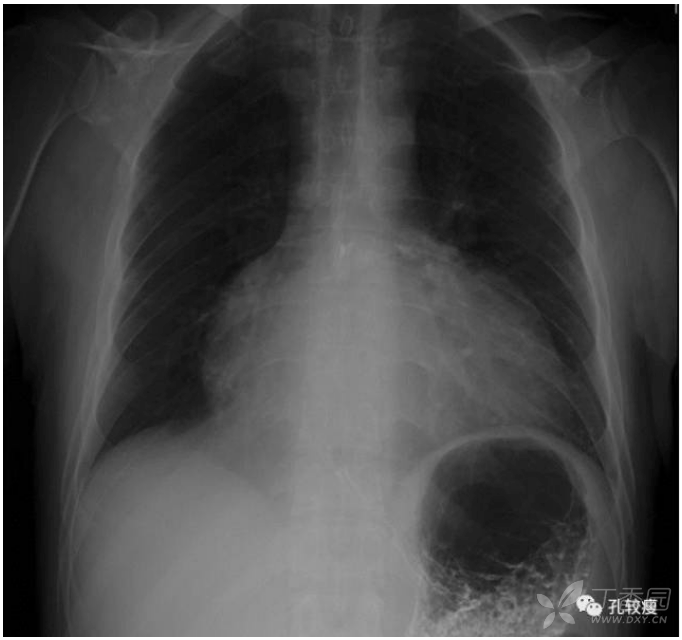

手机文件夹 (2)肺血减少 主要表现为肺纹理变细,稀疏,肺野透亮度增加

栓塞近侧肺血管扩张增粗,远端突然消失,远端肺野的透亮度增高,纹理

小儿单侧肺异常透亮综合征